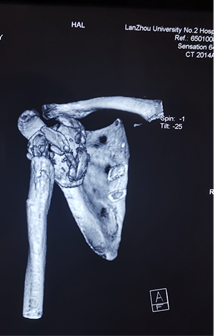

术前个性化定制3D打印-反肩关节置换假体,结合病情设计修补重建及定位点

韵向东主任考虑到患者年龄较轻,生活质量要求较高,为了最大限度地恢复保留患者的肩关节功能,决定结合与国际接轨的3D打印数字化假体最新技术,个性化定制了反肩关节假体,降低了因关节畸形及缺损,周围肩袖缺失等增加的手术难度及风险,同时也大大缩短了手术的时间,让反肩置换更加精准,患者满意度大幅度提高!